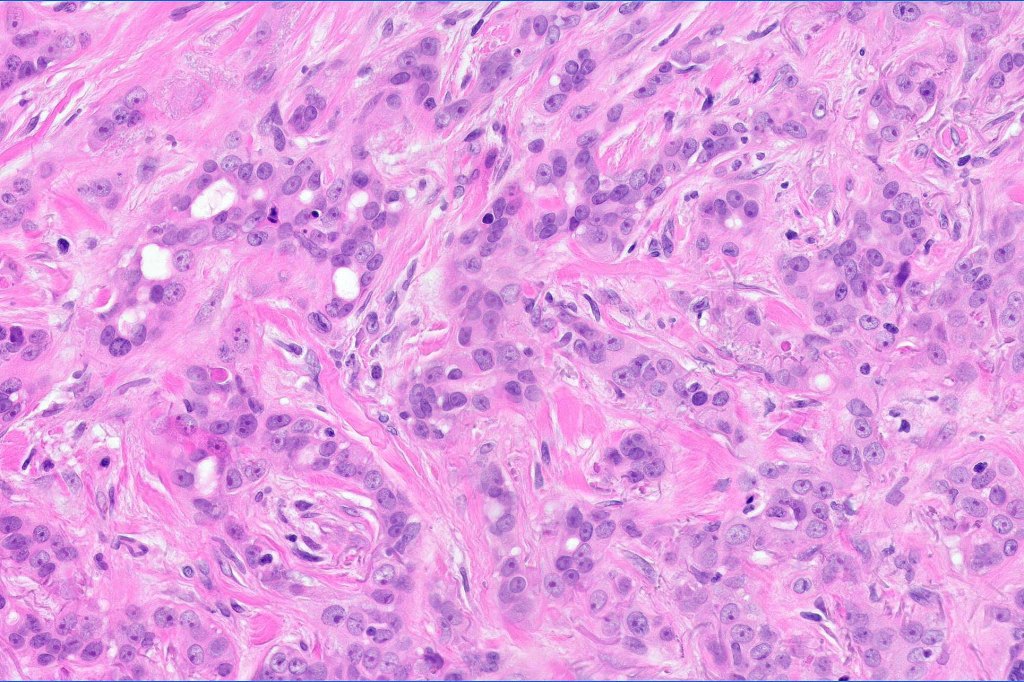

•Widely infiltrating biphasic tumor

•Superficial SCC

•Adenocarcinoma in deeper reaches

•Variable pleomorphism and mitotic activity

•Deep part may show both ducts and glands

•Often extends to the subcutaneous fat

•Perineural infiltration is commonly seen